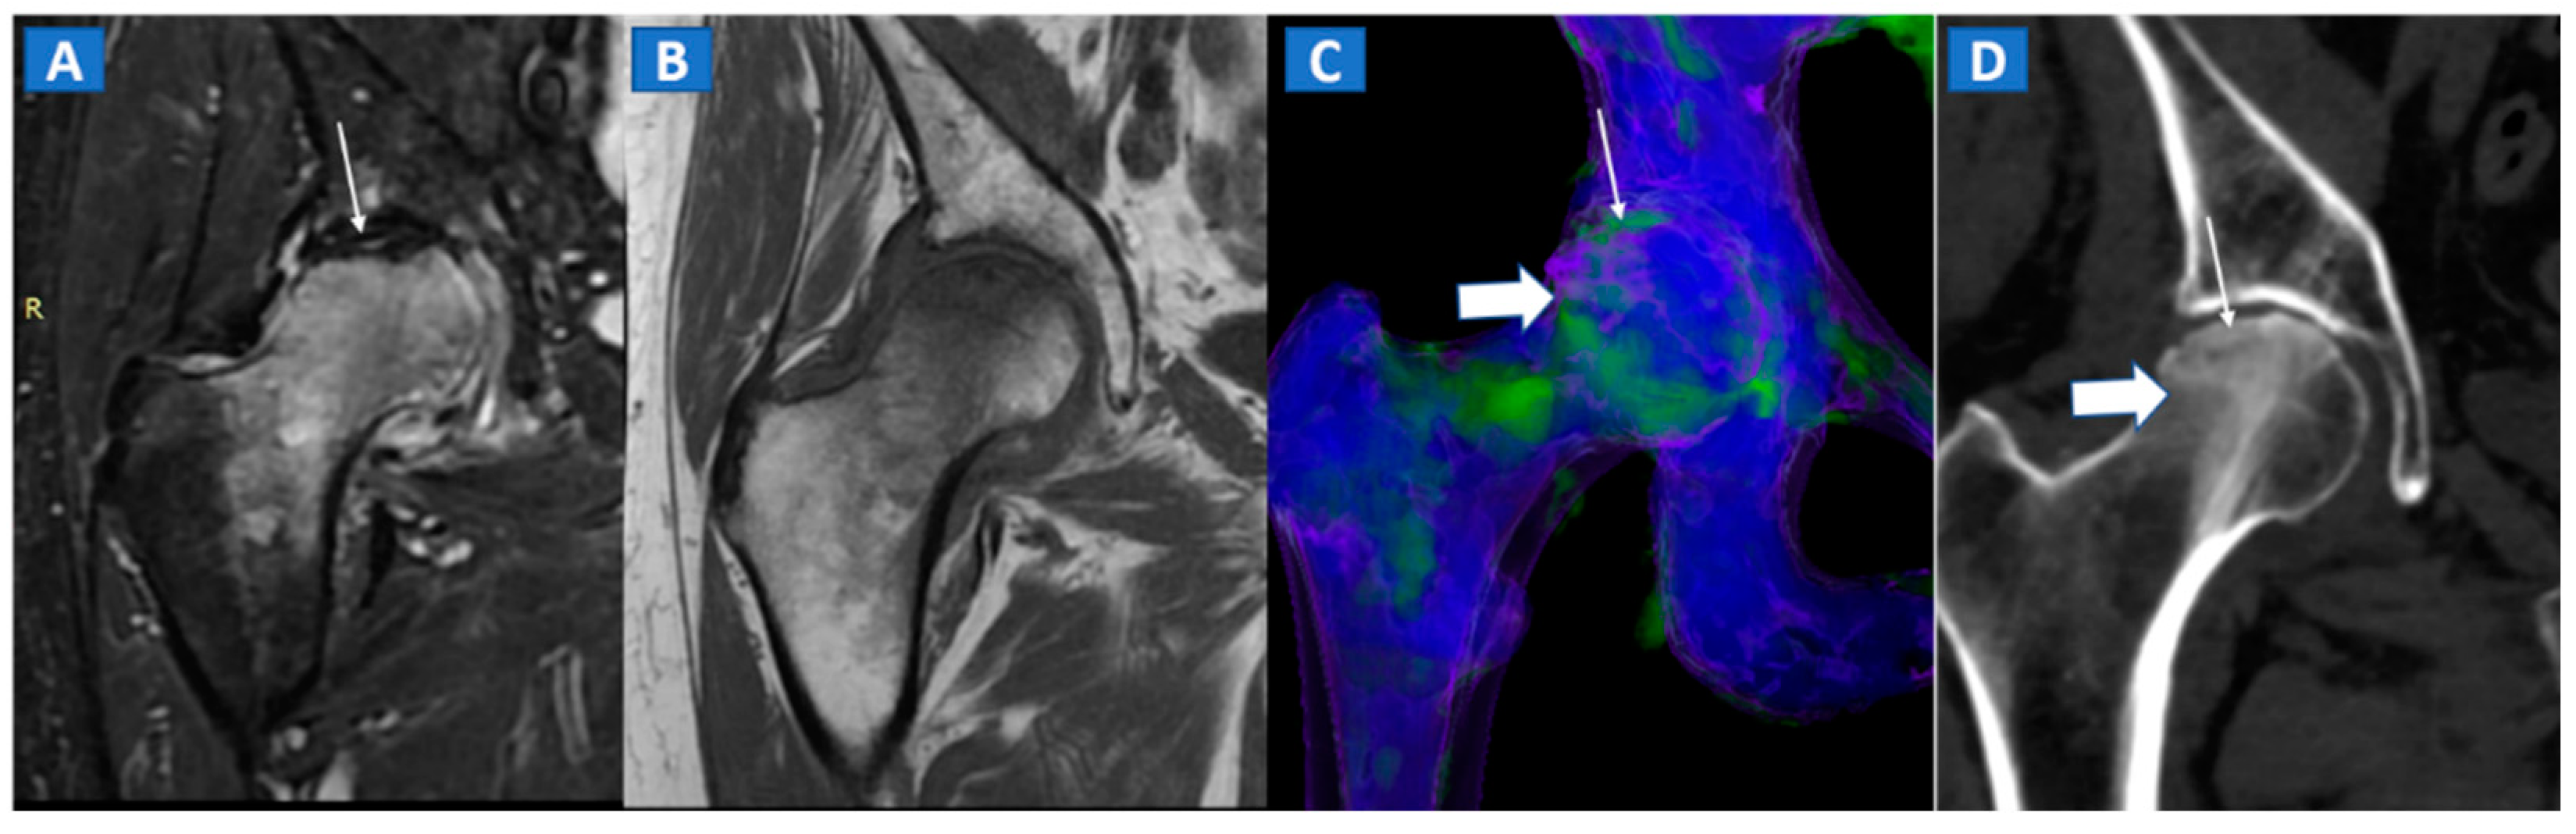

7. Avascular Necrosis